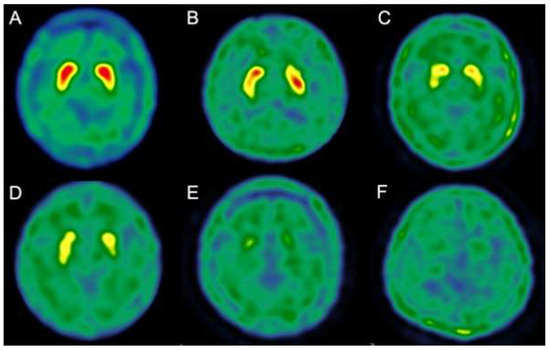

2.2.2. 99 mTc-TRODAT-1 SPECT

| 99 mTc-TRODAT-1 stages | |

| Average | 2.1 ± 1.2 (0~4) |